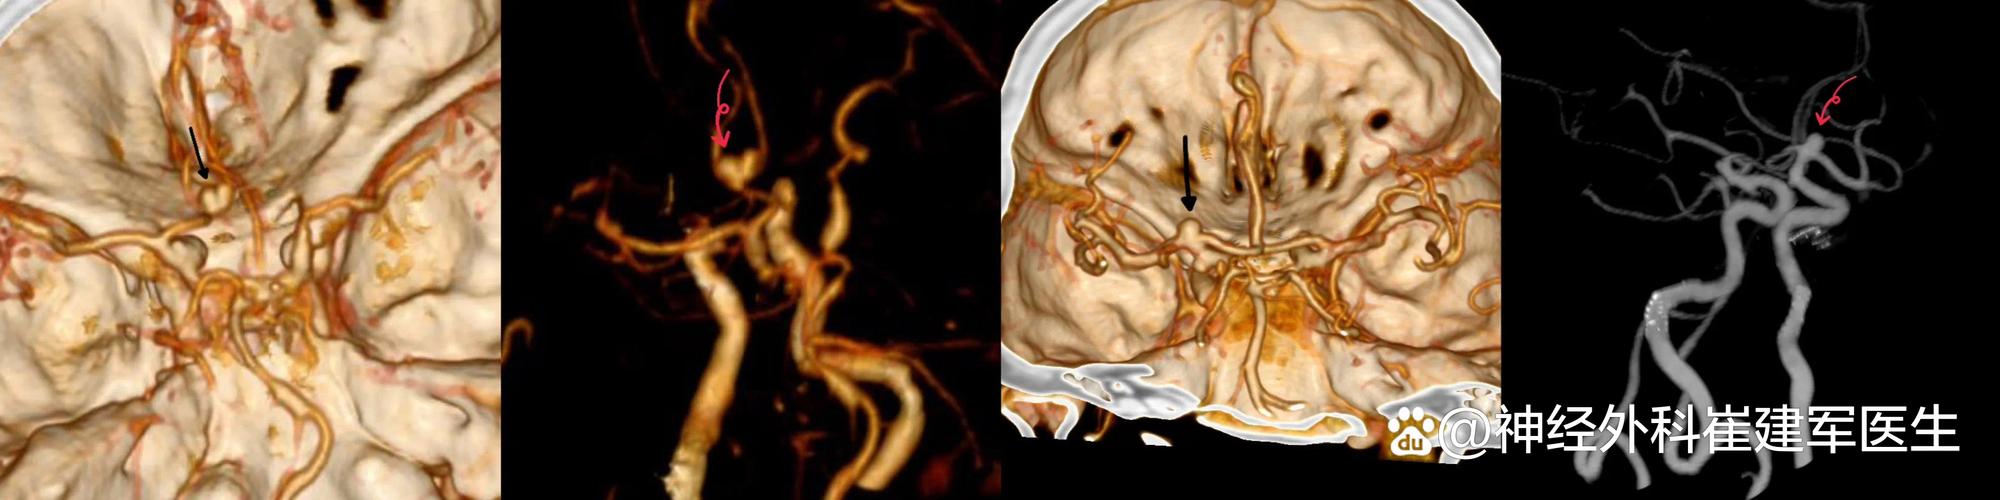

您可以把它想象成一种特殊的CT检查,它通过向患者静脉内注射一种特殊的造影剂(一种含碘的液体),这种造影剂会随着血液循环流遍全身的动脉血管,包括脑血管,CT设备会快速对头部进行连续扫描,最后利用计算机软件将采集到的数据重建成一幅幅清晰的脑血管“三维图像”。

CTA就是给您的脑血管拍“高清立体照片”和“动态电影”。